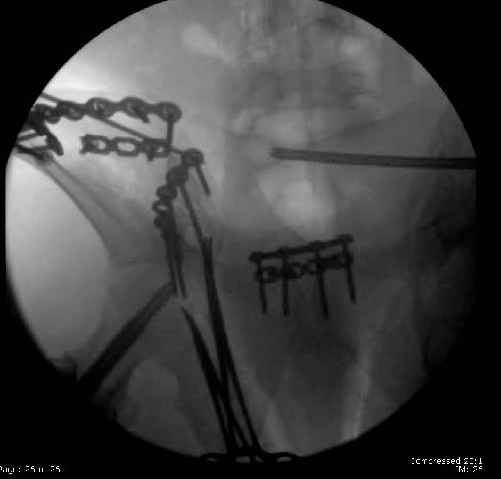

Here are the postop fluoros.

Fluoroed L SI joint and it seemed stable, but wide. So, applied c-clamp to try to squeeze down L SI joint (and note, on the last slide attached, that it's still wide), and got it closer. Single perc Iliosacral screw 40mm thread.

So, there I was with the aforementioned info on my mind, and my R iliac wing was a little malreduced. I think it's in residual extension and some external rotation, explaining the 5-6mm gap/step

on the posterior R iliac wing. (When I loooked at the inlet fluoro, the L obturator foramen was more visible than the R obt foramen, as was the R ischial spine) so it's not as stable as if it were

anatomic, despite all the metal. This came from hesitance to take down all the posterior paraspinals to really see the R posterior crest (where the malreduction is best seen on the iliac oblique view), and I could see the entire iliac fossa and most of the crest anyway.

Finally, the L SI joint seemed wide, even after closing it with c-clamp and iliosacral screw, so I added the extra 4 hole symphyseal plate anteriorly (even though to my knowledge unproven). That was the thinking and sequence of events that lead to the 2 symph plates shown. Note that the 4 hole recon is a locking plate (non-locked in medial 2 holes before locked screws in holes 1 & 4) -- fertile ground for debate on that I'm sure!